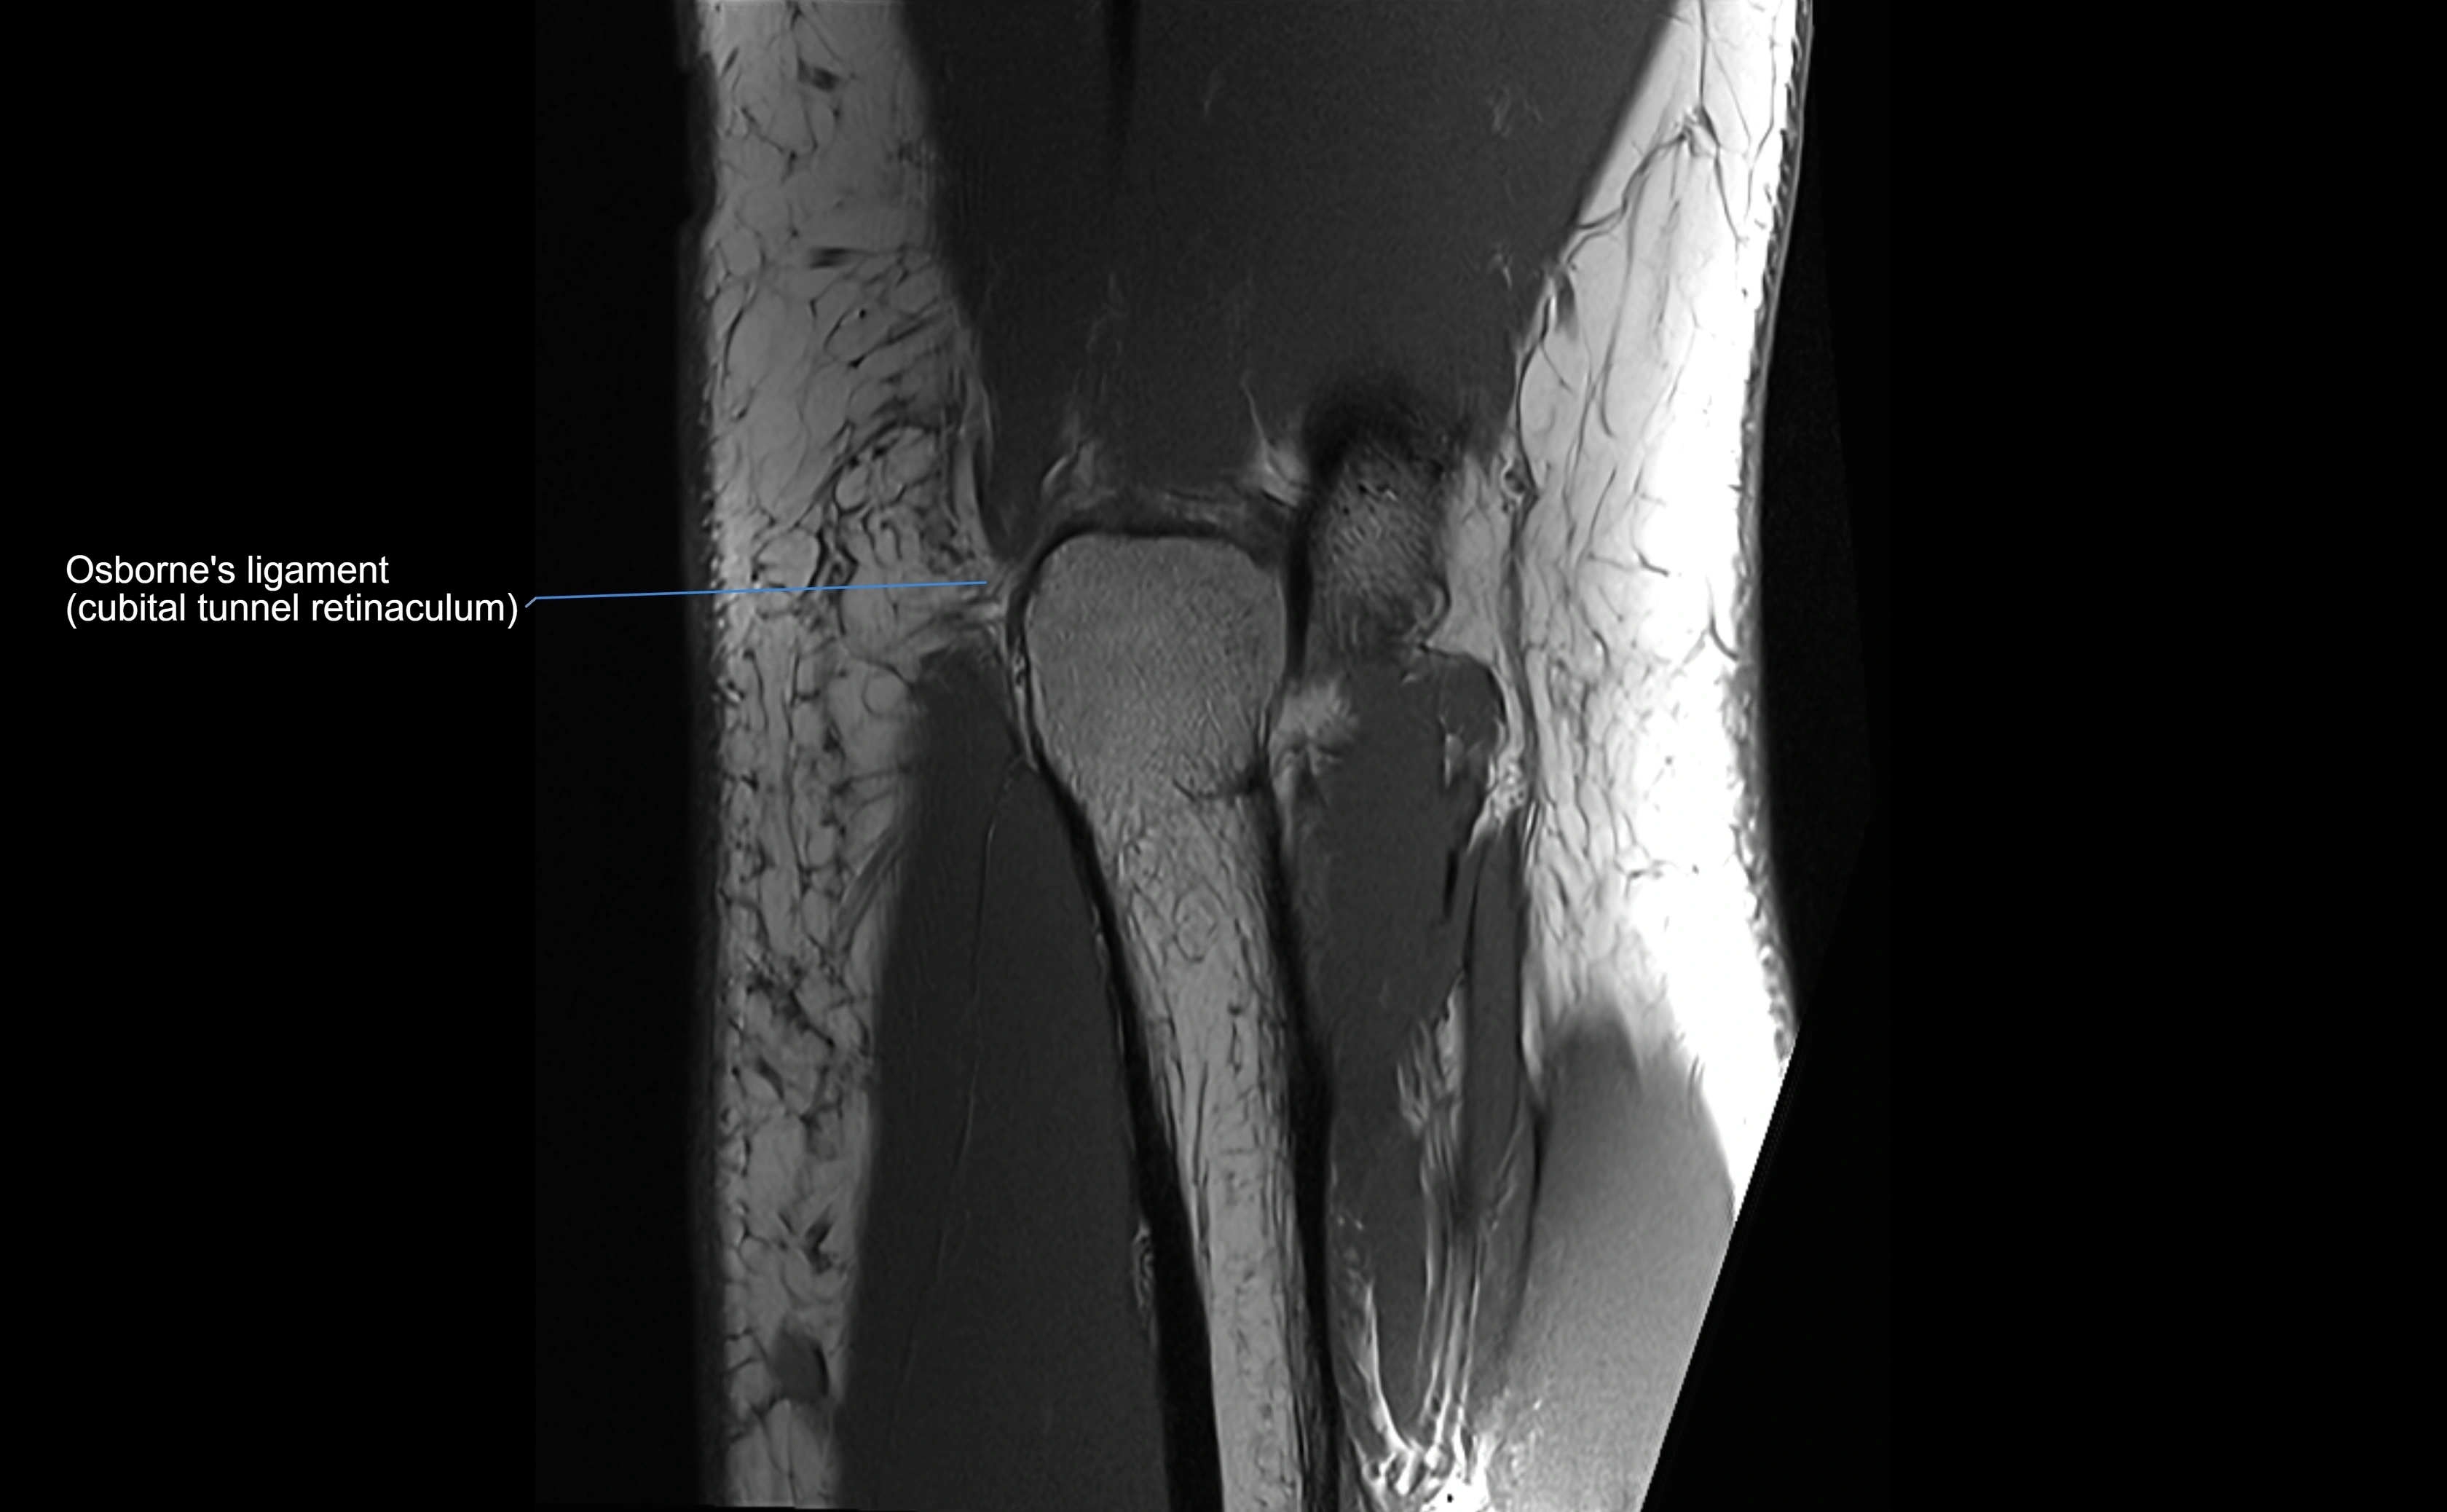

MRI images

image